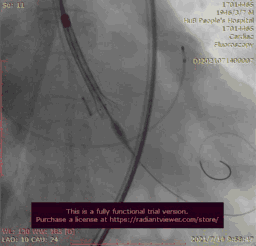

在放射科,超声科和麻醉科的通力协作下,顺利完成了术前准备,术者团队在术中谨慎建立轨道,根据主动脉根部造影的结果选择合适的跨瓣体位。

主动脉根部造影

输送器跨瓣

瓣膜稍高位释放